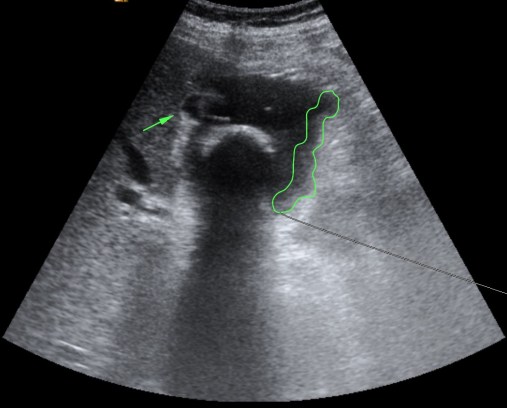

Se realiza ecografía abdominal:

En sucesivos cortes observamos lo siguiente:

Se observa una mala evolución radiológica. Dada la clínica del paciente y los hallazgos ecográficos podemos concluir que estos hallazgos son compatibles una colecistitis xantunogranulomatosa litiásica sobreinfectada (que se confirmó posteriormente con anatomía patológica).

- Colecistitis xantunogranulomatosa: nódulos o bandas intramurales. Se producen por la oclusión de los senos de Rokitansky Aschoff de la pared, los cuales se rompen, luego la bilis coloniza la pared y finalmente produce una reacción inflamatoria a la que puede sobreañadirse una infección. Es un factor de riesgo para el carcinoma.

- Eco y TC: Litiasis + engrosamiento mural focal o difuso. Puede haber cambios inflamatorios pericolecísiticos. Los nódulos hipocogénicos o bandas pueden sugerir el diagnóstico específico de c. xantunogranulomatosa.

- El diagnóstico raramente se realiza previo a la cirugía y al análisis histopatologíco.